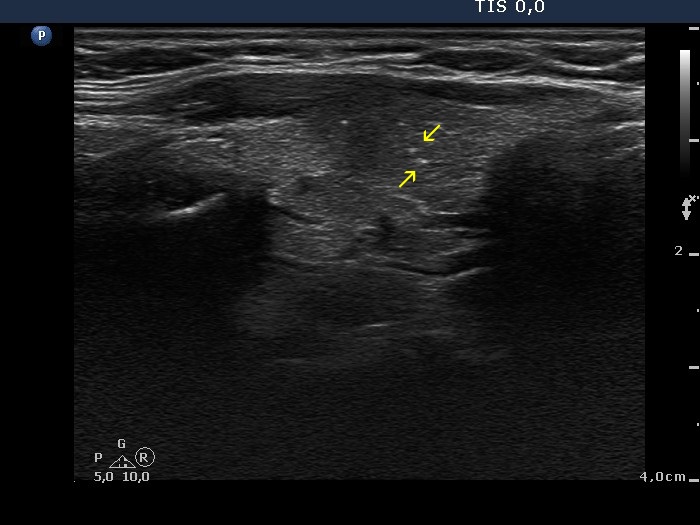

Papillary carcinoma (histology) - case conp035

Transverse scan

Longitudinal scan

It seems to be evident that the borders of this lesion pointed with yellow arrows are irregular. On the other hand, it is difficult to group into one or another well-characterized subgroup of pathological borders. Green arrow points to a lobulated part while red arrows do to spiculated parts of the tumor.